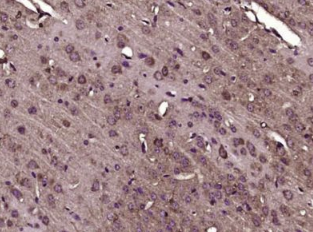

多聚甲醛固定,石蜡包埋(小鼠脑);用柠檬酸钠缓冲液(pH6.0)煮沸15min;用3%过氧化氢阻断内源过氧化物酶20分钟;阻断缓冲液(正常山羊血清)37℃30min;抗体(AdAMTS7(NT))多克隆抗体在1:400 OV下孵育在4°C下加热,然后根据SP试剂盒(兔子)说明和DAB染色进行操作。